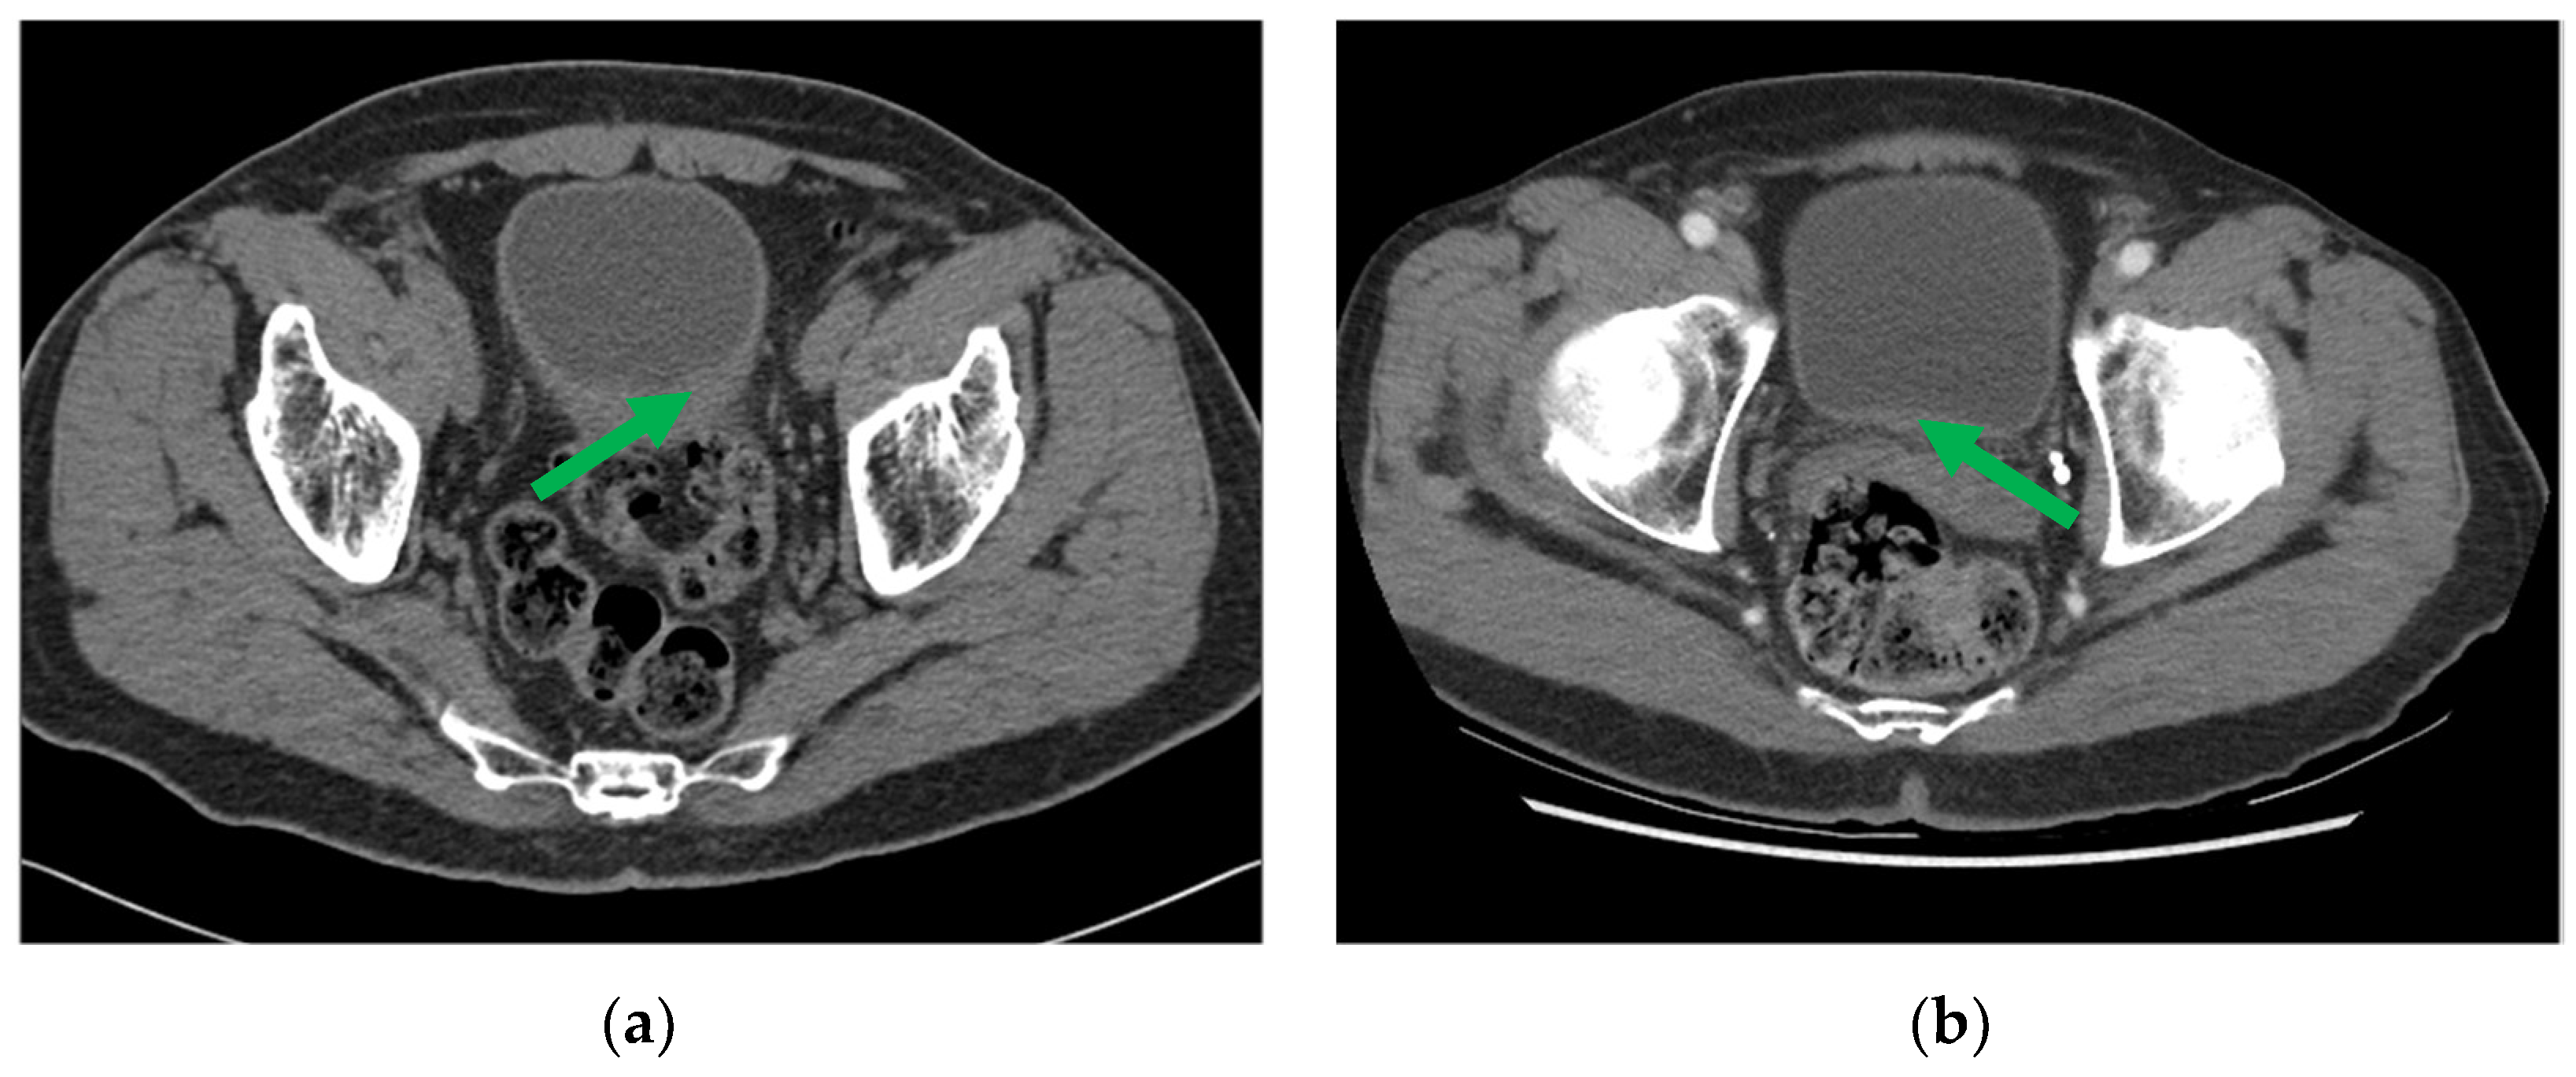

One example of pre- and post-chemotherapy CTU scans of bladder cancer can be found in Figure 3. The CTU scans used in this study were acquired with GE Healthcare LightSpeed MDCT scanners, Issaquah, WA, USA, set at 120 kVp and 120–280 mA, with the slice interval ranging from 0.625 to 5 mm. The CTU series with the comparatively best quality were utilized regardless of whether they were performed after administration of contrast material or were non-contrast images. The contrast-enhanced CTU scans were obtained 12 min after the initiation of the first bolus of a split-bolus IV contrast injection, and 2 min after the initiation of the second bolus of 175 mL of nonionic contrast material at a concentration of 300 mg iodine/ml.

Figure 3. CTU images of a bladder cancer patient (a) pre- and (b) post-neoadjuvant chemotherapy, with the initial and residual cancer indicated by the green arrow.